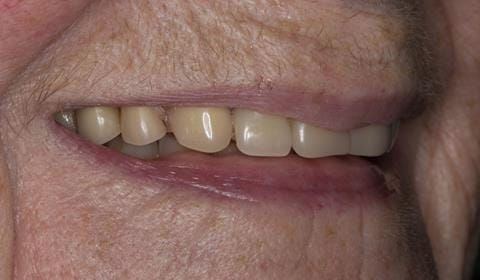

The 'gasket' or 'window' denture - provision of a maxillary cobalt chromium based partial denture

- Poorly fitting cobalt chromium based maxillary partial denture, which has been added to. This exhibited poor retention, stability and tissue fit (support). Unable to wear a new acrylic based denture.

Following consultation and second discussion appointment the patient chose to have option 2 namely, a window denture - maxillary cobalt chromium based partial denture. The clinical situation and treatment process is shown in detail below with photographs. The patient was successfully rehabilitated with this and her quality of life considerably improved. The clinical work was provided by Finlay and the technical work by Rowan.